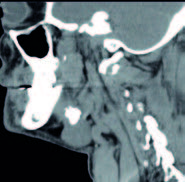

La TAC del cuello señala una litiasis submaxilar derecha: ligero aumento del tamaño de la glándula submaxilar derecha observándose en su interior calcificación de 19 x 15 x 15 mm y otras dos pequeñas adyacentes (de 4 y 5 mm respectivamente). No se observan colecciones a nivel de la glándula submaxilar. No se observan otros hallazgos a nivel de laringe o faringe. Sin imágenes ganglionares de tamaño significativo a nivel de las cadenas ganglionares cervicales.

FIGURA 3: Corte tomográfico sagital.